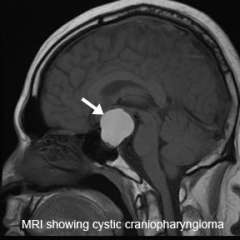

Your doctor may order a high-resolution magnetic resonance imaging (MRI) scan. This test is valuable because it allows the neuroradiologist to view the tumor from different angles.

In some cases, a powerful 3T (Tesla) MRI scanner can help define the location of critical brain structures affected by the tumor.

A computed tomography (CT) scan is also a good diagnostic tool as it detects calcification in the tumor